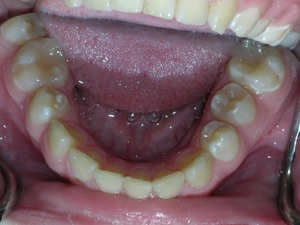

Here’s a fascinating case of a young lady who had a completely blocked out premolar.

With a combination of braces, expansion and trimming we were able to bring it in. Watch!